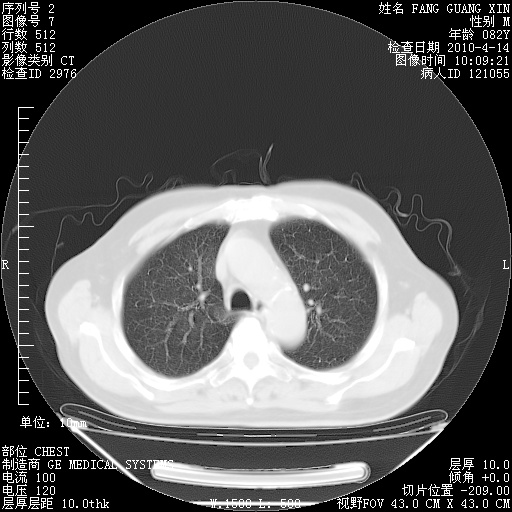

4月14日肺部CT